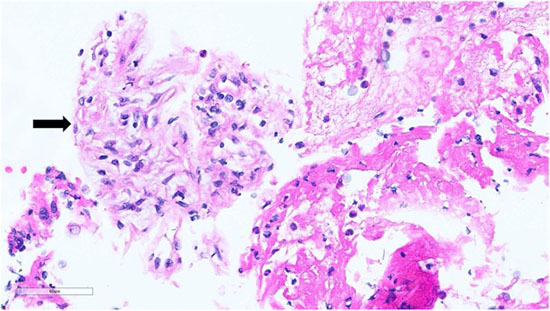

Figure 2: Lung FNA, Cell Block, Hematoxylin and eosin stain: epithelioid histiocytes and lymphocytes suggestive of ill-formed granuloma (black arrow)

Figure 3: Lung FNA, Cell Block, Hematoxylin and eosin stain: foamy amorphous materials (black arrowheads), Cryptococcus organisms (white arrowheads), with histiocytes and lymphocytes.